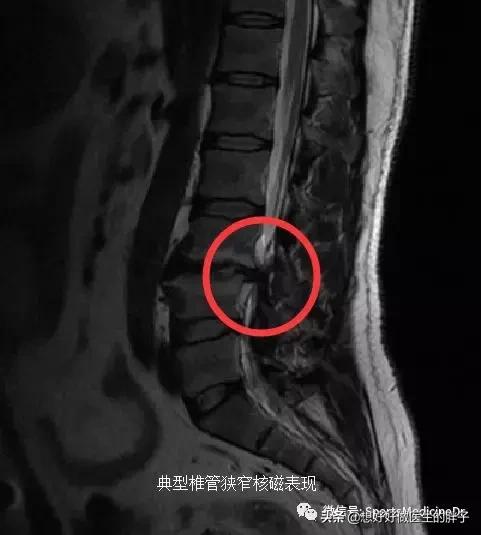

开始今天的文章之前,想请大家看看一个我最近患者的几张核磁片子,当这个患者进入诊室的时候,我的第一印象是这个人身材真好,四十多岁的年纪,虎背熊腰的,特别健壮!但是他表情异常痛苦,走路的时候一瘸一拐的,当时我就觉得这个人可能是伤到腰了。果不其然,他的主诉确实就是腰痛,而且已经三个月了,腰痛越来越重,近几日更是开始出现了明显的下肢疼痛,步行超过200米就要休息一下。鉴于这个患者出现了明显的椎管狭窄和神经卡压的症状,给与其检查了核磁,结果如下,(说句实话,看到他的核磁我是比较惊讶的):

这是典型的腰椎间盘突出、椎体轻度滑脱并伴有椎管狭窄的核磁表现,但是一般腰突的患者最常见的椎间盘突出节段在腰4-5或者腰5-骶1节段,为什么这个患者出现在腰3-4节段呢?而且这个患者的腰3-4间隙明显的出现了过度的骨质增生,完全不像是40岁患者的核磁表现。